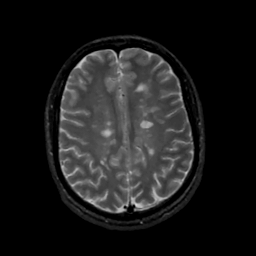

MR Study #15, June 9, 1991 -- Slice #34

[Home][Help][Clinical][Tour 1][Tour 2] Slice 34